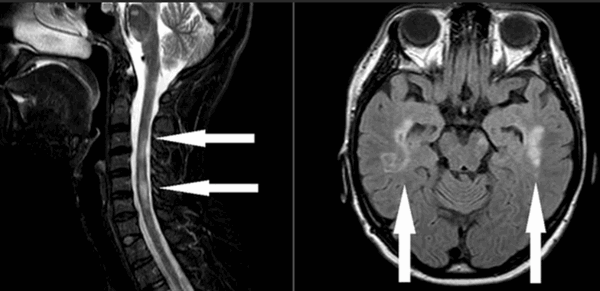

На МРТ классически выглядит как «обод» низкой интенсивности по поверхности головного или спинного мозга, что хорошо видно на последовательностях градиентного эха или SWI-последовательностях.

Для выявления поверхностного сидероза МРТ является методом выбора. Признаки весьма специфичные - мягкая мозговая оболочка и эпендимальная поверхность из-за скоплений гемосидерина имеют низкую интенсивность сигнала, особенно в области ствола мозга и мозжечка (червь и листки мозжечка - наилучшие места для выявления отложений). В давних случаях может наблюдаться атрофия мозжечка.

- Т2: снижение интенсивности;

- Т1: снижение интенсивности;

- Т2*: снижение интенсивности сигнала вплоть до его выпадения;

- SWI: снижение интенсивности сигнала вплоть до его выпадения;